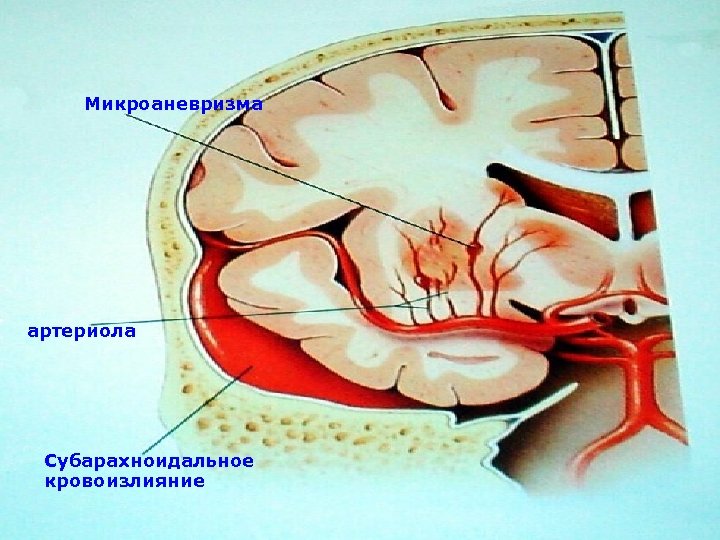

Микроаневризма артериола Субарахноидальное кровоизлияние

Микроаневризма артериола Субарахноидальное кровоизлияние